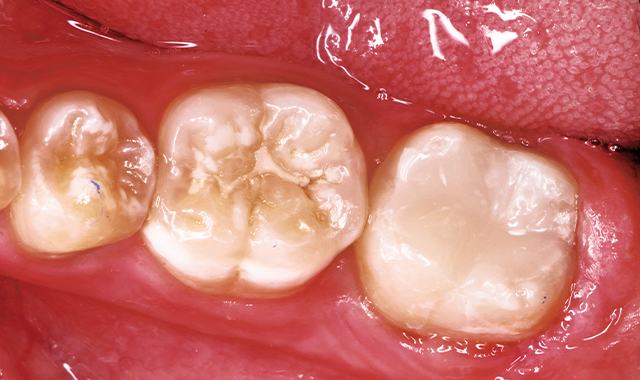

A 14-year-old patient presented to our office for a new patient examination. He had just completed orthodontic treatment and he had several large posterior caries and areas of defective enamel on his anterior and posterior teeth (Figs. 1-5). After a thorough examination and consultation with the patient and father, it was determined that the large caries on teeth #14DO, 18OB and 31OB should be sealed with large fillings, the defective enamel be treated with CTx4 toothpaste and CTx3 oral rinse (CariFree), and monitored as he gets older. The patient was appointed for caries removal and direct restorations to be placed at his next visit.

Fig. 1 Fig. 2